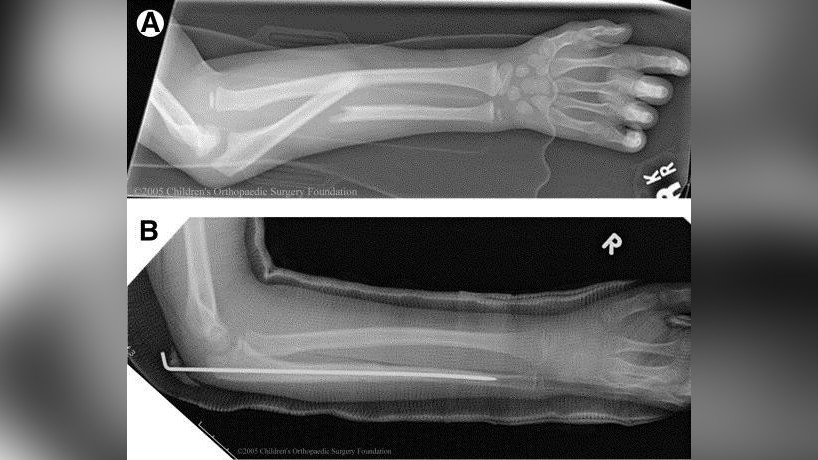

Перелом Галеацци у ребенка: полное руководство по лечению и восстановлению

Если ваш ребенок получил перелом предплечья, важно понимать все этапы лечения. В этой статье детский ортопед подробно объясняет, что такое перелом Галеацци, какие методы лечения существуют и как обеспечить полное восстановление функции руки.